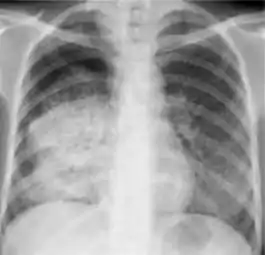

5. Hilar or mediastinal lymphadenopathy (bihilar lymphadenopathy) - Enlargement of lymph nodes in one or both hila or within the mediastinum, with or without associated atelectasis or consolidation.

Chest x-ray showing bilateral hilar adenopathy of primary pulmonary TB